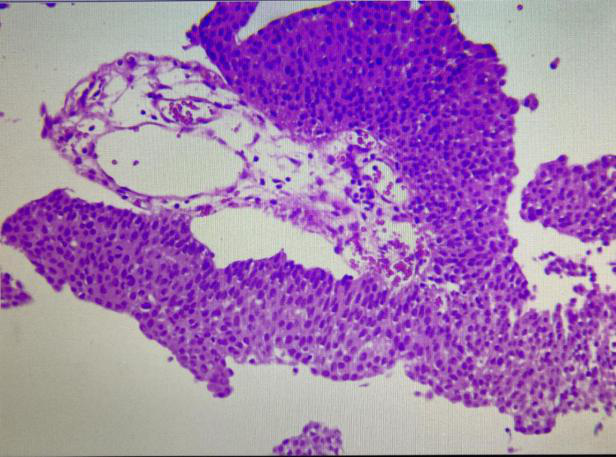

低級(jí)別乳頭狀尿路上皮癌,細(xì)胞和組織結(jié)構(gòu)較規(guī)則。細(xì)胞排列緊密,維持正常極性,但有明顯的小灶狀核異型性改變,表現(xiàn)為核濃染、少量核分裂象(多見(jiàn)于基底部)和輕度核多形性。